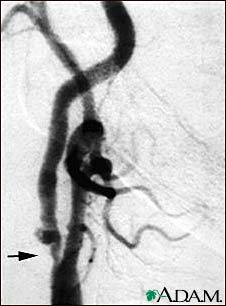

This is an angiogram of the right carotid artery showing a severe narrowing (stenosis) of the internal carotid artery just past the carotid fork. There is enlargement of the artery or ulceration in the area after the stenosis in this close-up film. Note the narrowed segment toward the bottom of the picture.